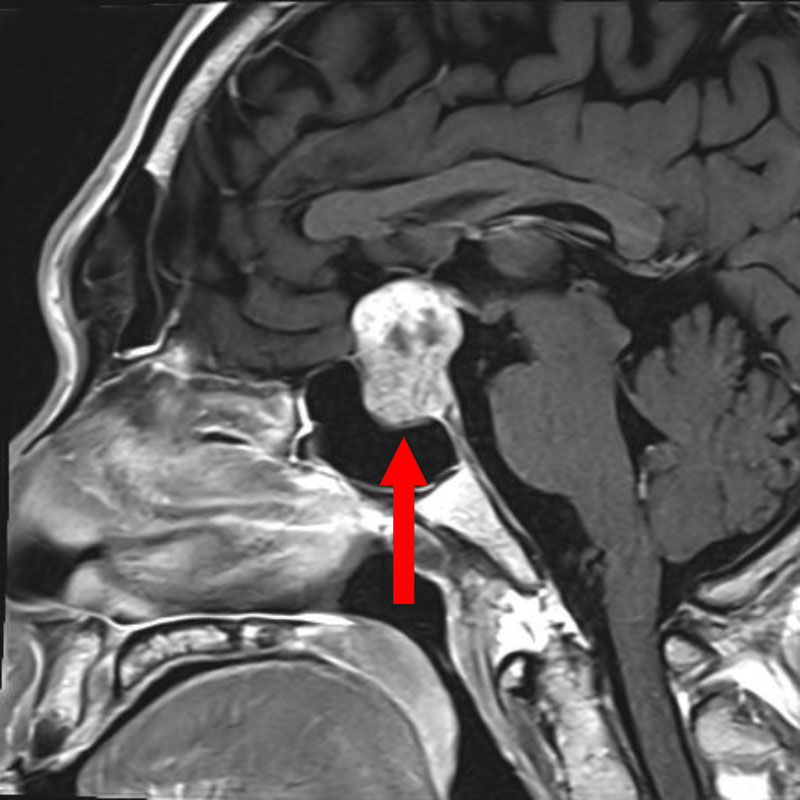

703

'25年12月

50代

先端巨大症

頭蓋内腫瘍摘出術

No.’25_105 手術前1

No.’25_105 手術前2